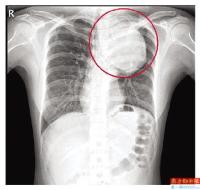

• 吵架生气就可能引爆的人体“不定时炸弹”

吵架生气、上个大号、赶个公交、爬层楼梯就可能引爆的人体“不定时炸弹”,深圳90后小茹最近不幸查出体内长了一个大青芒一般的瘤子,医生说这虽然不是肿瘤,却比肿瘤更凶险,随时会危及生命。可她跑了多家医院